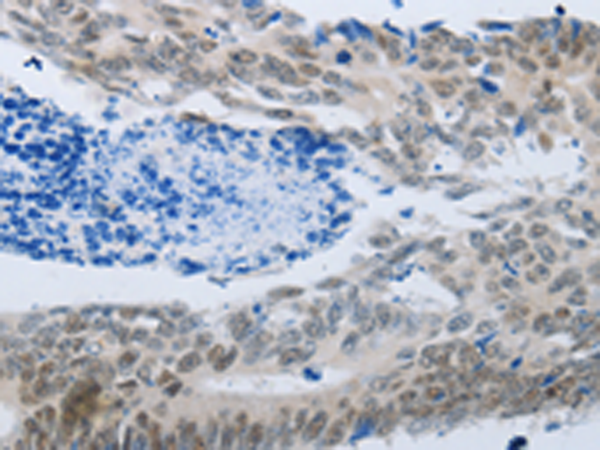

分类: 科研抗体货号: P11043别名: TBM; leB; MUC5; mucin应用: IHC反应种属: Human